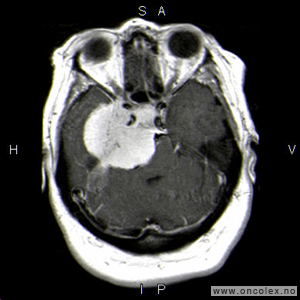

Knosp klassifikasjon brukes for å beskrive svulstenes utbredelse fra midtlinjen og ut til sidene. Klassifikasjonen deler svulstene inn i grad fra 0 til 4, hvor grad 0 er svulster i hypofysegropen uten utbredelse inn i sinus cavernosus, og grad 4 er svulster som omslutter den indre halsarterien (arteria carotis interna). Grad 4 svulster og svulster som brer seg ut til siden for den indre halsarterien (Knosp grad 3) er svært vanskelig å fjerne fullstendig med operasjon.

Bildeserie av stadieinndeling av hypofysesvulster (Knosp klassifikasjon)